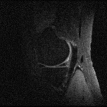

Table 1 shows the performance of both approaches on the test data, in addition to the error lower-bounds obtained by the best -sample approximations with respect to the Fourier basis. It appears that the learning based approach slightly outperforms the randomized variable density based approach.

However, the slight numerical improvements are actually accentuated when we look at the details of reconstructions, shown in Figure 2 for the test Patient #13. It is clear that the learning-based reconstructions provide more details especially for and .